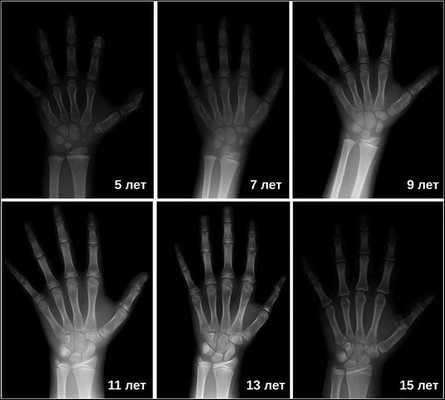

Основной симптом — отставание в темпах линейного роста [2] . Такие дети вырастают менее чем на 4 см в год. Нарушение динамики роста будет заметно уже в первые месяцы жизни ребёнка. Если повреждение гипоталамуса или гипофиза возникло в более позднем возрасте, то отставание в росте будет отмечаться позднее. Также для детей с гипофизарным нанизмом характерно отставание костного (биологического) возраста от паспортного (фактического) более чем на 2-3 года.

Затем врачи определяют костный возраст. Сделать это можно с помощью рентгена или УЗИ запястья. В норме костный возраст может отставать или опережать паспортный на два года.